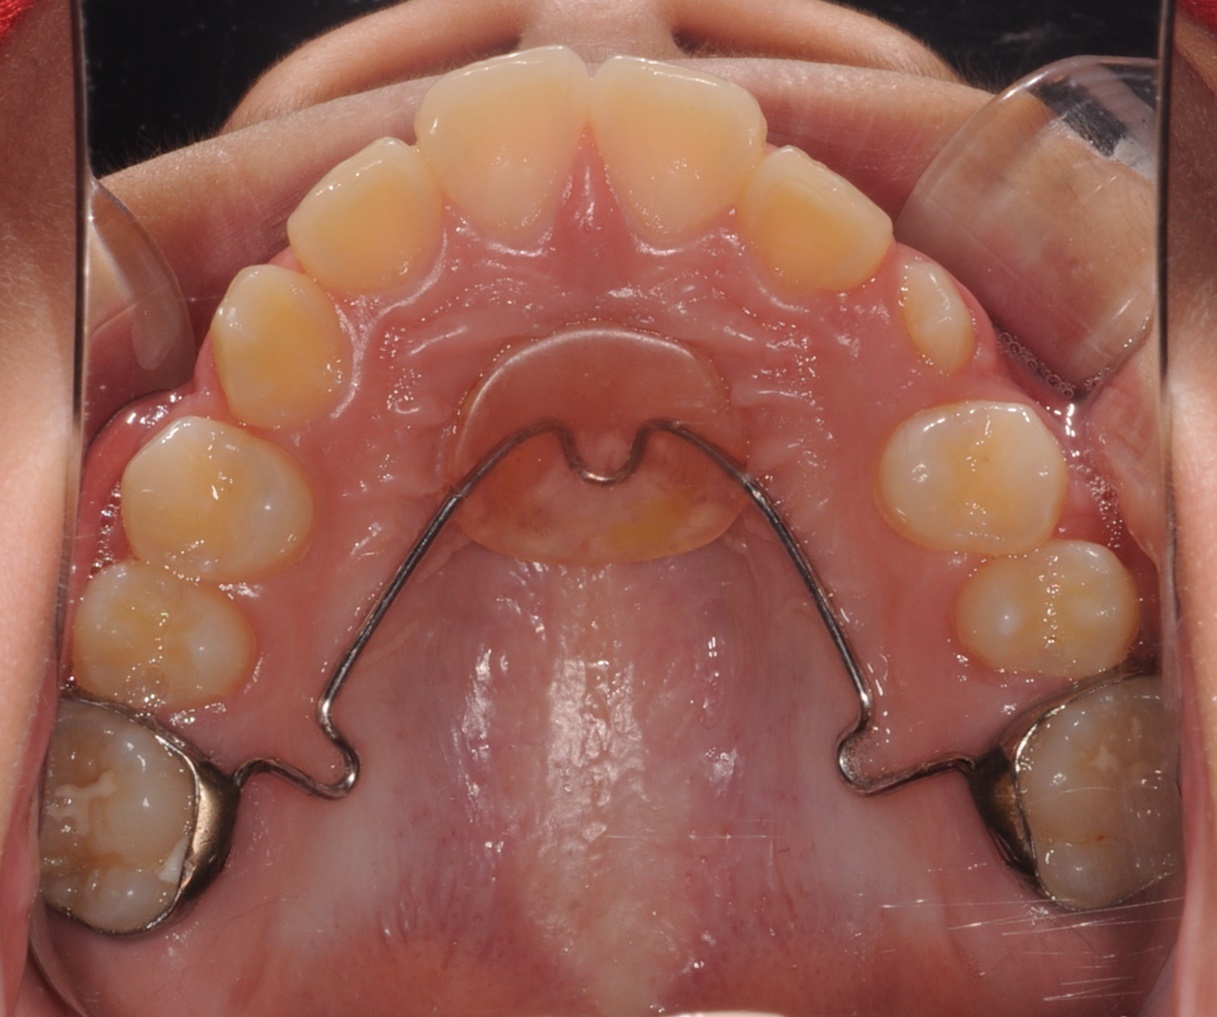

L-A (Lingual arch)

하악에서 유치의 조기발거 시

영구치 맹출시기까지 공간을 유지합니다.

유치 조기 소실로 인한

영구치 맹출공간 부족을 방지합니다.